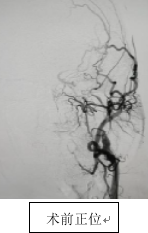

入院后,神经内科一病区王建峰主任团队迅速邀请神经外科、麻醉科及影像科等多学科举行会诊,经各项必要检查,会诊专家发现,朱先生的状况十分棘手,他的慢性闭塞血管内壁已经硬化、狭窄甚至完全堵死,状态犹如风化后的塑料薄膜,稍有外力干扰,可能会立刻崩溃。如果采用传统介入方式治疗,将极难找到通路,因此手术风险极大。

面对患者跨国就医的信任,神经内科一病区必须迎难而上,只有手术成功才能回应朱先生及家人的热切期望。在多学科会诊几番论证后,王建峰主任团队最终决定采用国内技术前沿的BASIS技术对朱先生的左侧颈部内动脉进行血管再通。

BASIS技术属于前沿技术,在陕西省的应用也相对较少,但王建峰主任团队却信心十足,长期对前沿技术与理念的应用,给了他们底气,此次手术正是利用此技术在慢性闭塞段精准建立通道的优势,通过特殊设计的取栓支架和导引方法,最大限度避免血栓脱落和脑梗加重的风险。

手术在局部麻醉下进行,王建峰主任亲自上台,操作精细,在BASIS技术辅助下,顺利通过闭塞段,成功恢复左侧颈内动脉血流。手术过程中未出现血栓脱落等并发症,术后患者生命体征平稳,已安全送回病房,在护理团队的共同努力下,朱先生恢复良好。